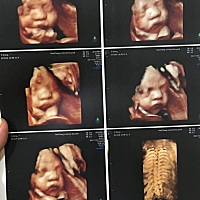

宝妈们都是多少周做的四维彩超